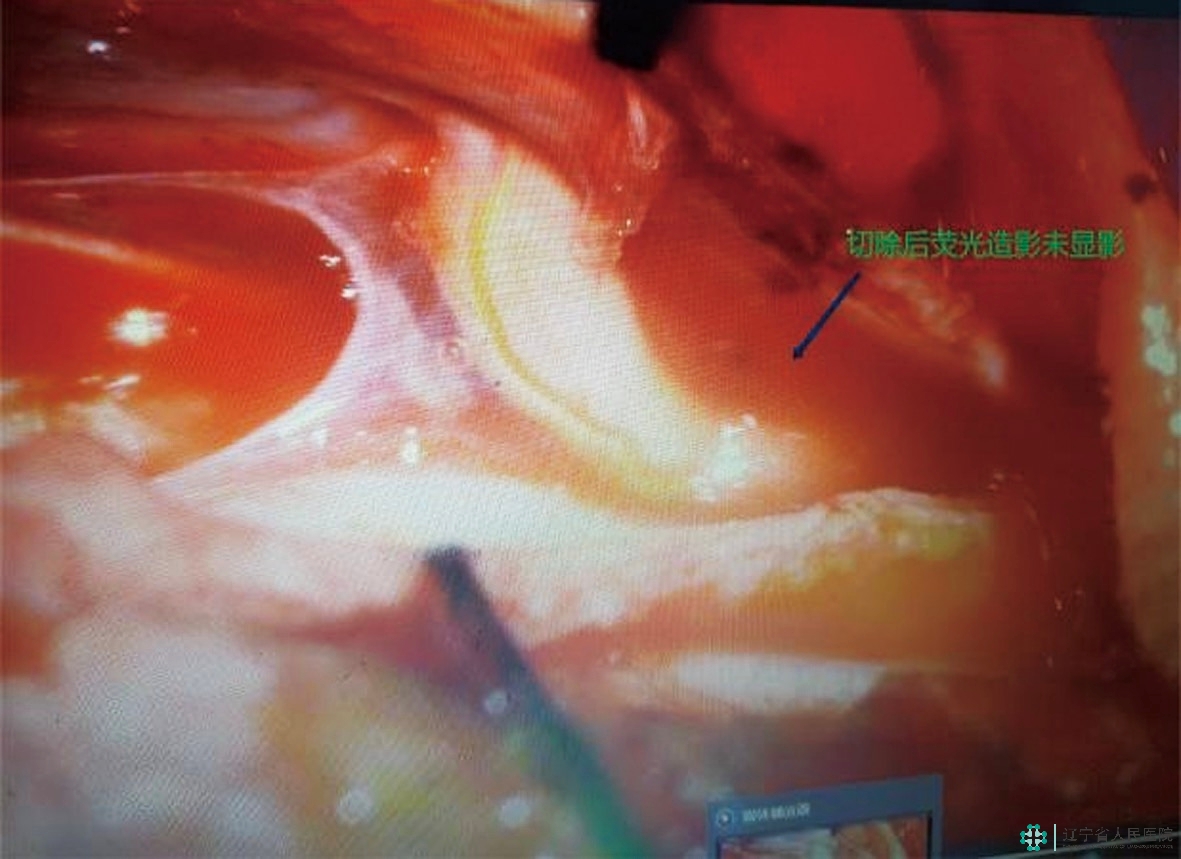

在这一系列环节中,精准定位、寻找瘘口至关重要,也是事关手术成败的最关键一步!臧培卓院长通过ZEISS KINEVO 900机器人手术显微镜独有的FLOW 800彩色荧光技术,使用一种特殊并且安全无毒的材料——吲哚菁绿(ICG),并凭借丰富的术中经验,顺利地确定了病变血管上瘘口的精确位置,为手术成功奠定了坚实基础。接下来,予以电凝后分离静脉、切除瘘口……手术顺利结束。

切断后,再次复查荧光造影,静脉未再显影,瘘口顺利封闭。截至发稿前,刘阿姨的双下肢乏力症状明显改善,已经可以站立行走,实现基本生活自理。